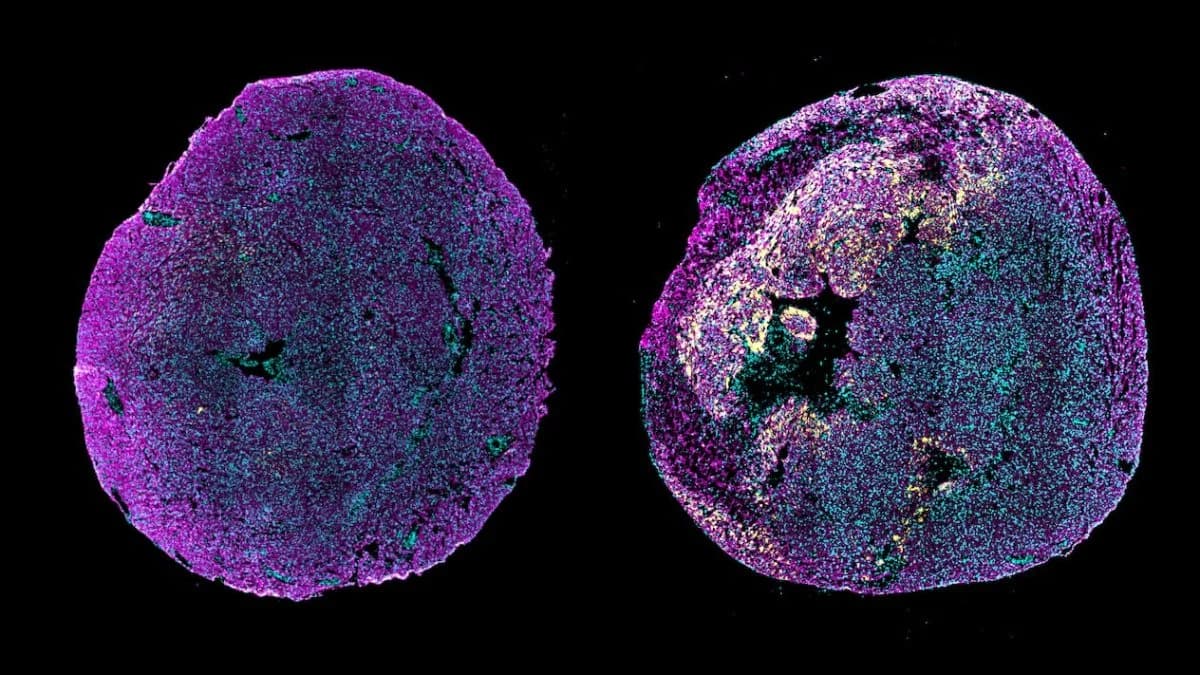

وأظهرت التجارب نجاحًا كبيرًا في تقليل الأنسجة الندبية وتحسين وظائف القلب، حتى في الحالات التي تأخر فيها العلاج لمدة أسبوع بعد الإصابة بمرض النوبة القلبية.